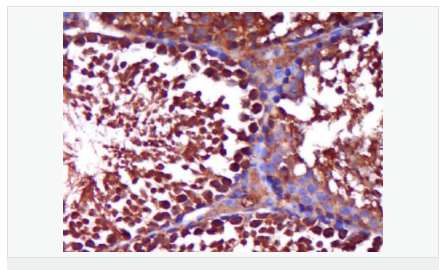

| 產(chǎn)品應(yīng)用 | WB=1:500-2000 ELISA=1:5000-10000 IHC-P=1:100-500 IHC-F=1:100-500 Flow-Cyt=1ug/Test IF=1:100-500 (石蠟切片需做抗原修復(fù)) not yet tested in other applications. optimal dilutions/concentrations should be determined by the end user. |

| 細(xì)胞定位 | 細(xì)胞核 細(xì)胞漿 |

| 產(chǎn)品介紹 | The androgen receptor gene is more than 90 kb long and codes for a protein that has 3 major functional domains: the N-terminal domain, DNA-binding domain, and androgen-binding domain. The protein functions as a steroid-hormone activated transcription factor. Upon binding the hormone ligand, the receptor dissociates from accessory proteins, translocates into the nucleus, dimerizes, and then stimulates transcription of androgen responsive genes. This gene contains 2 polymorphic trinucleotide repeat segments that encode polyglutamine and polyglycine tracts in the N-terminal transactivation domain of its protein. Expansion of the polyglutamine tract causes spinal bulbar muscular atrophy (Kennedy disease). Mutations in this gene are also associated with complete androgen insensitivity (CAIS). Two alternatively spliced variants encoding distinct isoforms have been described. [provided by RefSeq, Jul 2008] Function: Steroid hormone receptors are ligand-activated transcription factors that regulate eukaryotic gene expression and affect cellular proliferation and differentiation in target tissues. Transcription factor activity is modulated by bound coactivator and corepressor proteins. Transcription activation is down-regulated by NR0B2. Activated, but not phosphorylated, by HIPK3 and ZIPK/DAPK3. [ENZYME REGULATION] AIM-100 (4-amino-5,6-biaryl-furo[2,3-d]pyrimidine) suppresses TNK2-mediated phosphorylation at Tyr-267. Inhibits the binding of the Tyr-267 phosphorylated form to androgen-responsive enhancers (AREs) and its transcriptional activity. Subunit: Binds DNA as a homodimer. Part of a ternary complex containing AR, EFCAB6/DJBP and PARK7. Interacts with HIPK3 and NR0B2 in the presence of androgen. The ligand binding domain interacts with KAT7/HBO1 in the presence of dihydrotestosterone. Interacts with EFCAB6/DJBP, PELP1, PQBP1, RANBP9, RBAK, SPDEF, SRA1, TGFB1I1, ZNF318 and RREB1. Interacts with ZMIZ1/ZIMP10 and ZMIZ2/ZMIP7 which both enhance its transactivation activity. Interacts with SLC30A9 and RAD54L2/ARIP4. Interacts via the ligand-binding domain with LXXLL and FXXLF motifs from NCOA1, NCOA2, NCOA3, NCOA4 and MAGEA11. The AR N-terminal poly-Gln region binds Ran resulting in enhancement of AR-mediated transactivation. Ran-binding decreases as the poly-Gln length increases. Interacts with HIP1 (via coiled coil domain). Interacts (via ligand-binding domain) with TRIM68. Interacts with TNK2. Interacts with USP26. Interacts with RNF6. Interacts (regulated by RNF6 probably through polyubiquitination) with RNF14; regulates AR transcriptional activity. Interacts with PRMT2 and TRIM24. Interacts with GNB2L1/RACK1. Interacts with RANBP10; this interaction enhances dihydrotestosterone-induced AR transcriptional activity. Interacts with PRPF6 in a hormone-independent way; this interaction enhances dihydrotestosterone-induced AR transcriptional activity. Interacts with STK4/MST1. Interacts with ZIPK/DAPK3. Interacts with LPXN. Interacts with MAK. Part of a complex containing AR, MAK and NCOA3. Subcellular Location: Nucleus. Cytoplasm. Note=Predominantly cytoplasmic in unligated form but translocates to the nucleus upon ligand-binding. Can also translocate to the nucleus in unligated form in the presence of GNB2L1. Tissue Specificity: Isoform 2 is mainly expressed in heart and skeletal muscle. Post-translational modifications: Sumoylated on Lys-386 (major) and Lys-520. Ubiquitinated. Deubiquitinated by USP26. 'Lys-6' and 'Lys-27'-linked polyubiquitination by RNF6 modulates AR transcriptional activity and specificity. Phosphorylated in prostate cancer cells in response to several growth factors including EGF. Phosphorylation is induced by c-Src kinase (CSK). Tyr-534 is one of the major phosphorylation sites and an increase in phosphorylation and Src kinase activity is associated with prostate cancer progression. Phosphorylation by TNK2 enhances the DNA-binding and transcriptional activity and may be responsible for androgen-independent progression of prostate cancer. Phosphorylation at Ser-81 by CDK9 regulates AR promoter selectivity and cell growth. Phosphorylation by PAK6 leads to AR-mediated transcription inhibition. Palmitoylated by ZDHHC7 and ZDHHC21. Palmitoylation is required for plasma membrane targeting and for rapid intracellular signaling via ERK and AKT kinases and cAMP generation. DISEASE: Defects in AR are the cause of androgen insensitivity syndrome (AIS) [MIM:300068]; previously known as testicular feminization syndrome (TFM). AIS is an X-linked recessive form of pseudohermaphroditism due end-organ resistance to androgen. Affected males have female external genitalia, female breast development, blind vagina, absent uterus and female adnexa, and abdominal or inguinal testes, despite a normal 46,XY karyotype. Defects in AR are the cause of spinal and bulbar muscular atrophy X-linked type 1 (SMAX1) [MIM:313200]; also known as Kennedy disease. SMAX1 is an X-linked recessive form of spinal muscular atrophy. Spinal muscular atrophy refers to a group of neuromuscular disorders characterized by degeneration of the anterior horn cells of the spinal cord, leading to symmetrical muscle weakness and atrophy. SMAX1 occurs only in men. Age at onset is usually in the third to fifth decade of life, but earlier involvement has been reported. It is characterized by slowly progressive limb and bulbar muscle weakness with fasciculations, muscle atrophy, and gynecomastia. The disorder is clinically similar to classic forms of autosomal spinal muscular atrophy. Note=Caused by trinucleotide CAG repeat expansion. In SMAX1 patients the number of Gln ranges from 38 to 62. Longer expansions result in earlier onset and more severe clinical manifestations of the disease. Note=Defects in AR may play a role in metastatic prostate cancer. The mutated receptor stimulates prostate growth and metastases development despite of androgen ablation. This treatment can reduce primary and metastatic lesions probably by inducing apoptosis of tumor cells when they express the wild-type receptor. Defects in AR are the cause of androgen insensitivity syndrome partial (PAIS) [MIM:312300]; also known as Reifenstein syndrome. PAIS is characterized by hypospadias, hypogonadism, gynecomastia, genital ambiguity, normal XY karyotype, and a pedigree pattern consistent with X-linked recessive inheritance. Some patients present azoospermia or severe oligospermia without other clinical manifestations. Similarity: Belongs to the nuclear hormone receptor family. NR3 subfamily. Contains 1 nuclear receptor DNA-binding domain. SWISS: P10275 Gene ID: 367 Database links: Entrez Gene: 367 Human Entrez Gene: 11835 Mouse Omim: 313700 Human SwissProt: P10275 Human SwissProt: P19091 Mouse Unigene: 496240 Human Unigene: 39005 Mouse Unigene: 394224 Mouse Unigene: 439657 Mouse Unigene: 9813 Rat Important Note: This product as supplied is intended for research use only, not for use in human, therapeutic or diagnostic applications. AR是一個(gè)由917個(gè)氨基酸組成的蛋白質(zhì),位于雄激素靶組織細(xì)胞中或細(xì)胞表面上的特異分子部位或結(jié)構(gòu)。 AR在前列腺癌中起著重要的作用,研究表明AR的表達(dá)與組織分型形成一定的相關(guān)性 ,AR在高分化的腫瘤中表達(dá)較多,而在低分化的腫瘤中表達(dá)較少。用于前列腺癌的檢測,指導(dǎo)臨床治療,目前可用于乳腺癌、食道癌等各項(xiàng)腫瘤的研究。 |